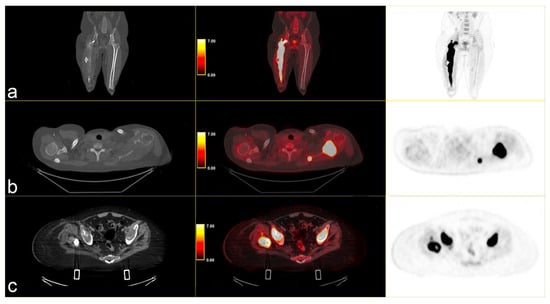

The patient continued third-line antineoplastic treatment with Gemcitabine (750 mg/mq) and Taxotere (75 mg/mq) for three cycles until disease progression. Fourth-line treatment with trabectedin (1.25 mg/m2) followed, reporting bone marrow and liver toxicity. The last PET scan, performed in May 2024, showed an increased uptake of FDG in several pseudonodular lesions in both lungs at the pleuro-parenchymal level (SUVmax 25.3 vs. 10.9), and in the left axillary lymphnodes (SUVmax 17.4 vs. 6.1). A new, unknown area of glucose hypermetabolism was depicted in the body of the pancreas (SUVmax 4.0), highly suspicious for metastasis. The lesion of the right femur extended to the whole bone, with other secondary lesions in the skull [Figure 4].

Figure 4.

(a) MIP PET/CT showing significant disease progression; (b) volumetric and metabolic increase of the lesion in the left scapula (SUVmax 35); and (c) multiple lesions in the upper lobes of both lungs (SUVmax 25.3) on (b,c) strips CT on the left, PET/CT fused images the middle and PET images on the right.